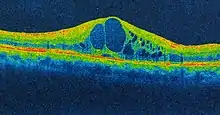

Cystoid macular edema (CME) involves fluid accumulation in the outer plexiform layer secondary to abnormal perifoveal retinal capillary permeability. The edema is termed "cystoid" as it appears cystic; however, lacking an epithelial coating, it is not truly cystic. The cause for CME can be remembered with the mnemonic "DEPRIVEN" (diabetes, epinepherine, pars planitis, retinitis pigmentosa, Irvine-Gass syndrome, venous occlusion, E2-prostaglandin analogues, nicotinic acid/niacin).